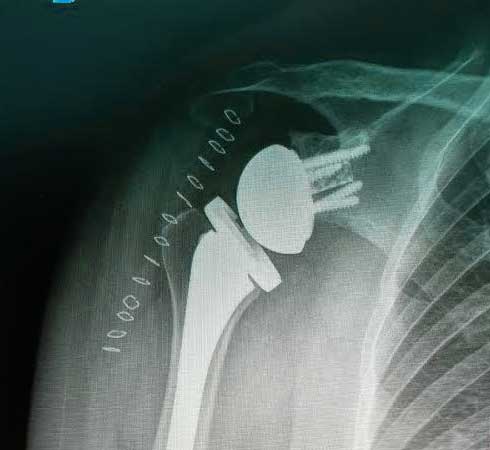

Prótesis de hombro

Es la sustitución artificial de la articulación por un implante de metal y polietileno indicada por artrosis, desgaste o lesión masiva del manguito rotador.

¿Por qué se realiza?

La razón más frecuente es aliviar el dolor intenso causado por artrosis, corregir las deformidades angulares en varo, valgo y contractura en flexión en adultos mayores y para adultos jóvenes, está indicada en lesiones crónicas articulares que ocasionan un desgaste acelerado.

Cuidados después de la intervención

En caso de tener una lesión asociada al deporte la recomendación es detener la práctica, reposar, aplicar frío y acudir con nosotros a una valoración ortopédica. La intención de una cirugía de hombro es mejorar la función de la articulación, así como recuperar los arcos de movimiento funcionales sin dolor y equiparado a la resistencia y la fuerza previa a la lesión.

Resultados esperados

La recuperación de la cirugía reemplazo de hombro con una prótesis reversa de hombro o una prótesis anatómica de hombro va muy ligada al estado de la articulación previamente lesionada y al apego que tenga el paciente con la terapia física y así poder ofrecer una recuperación buena, muy buena o excelente.